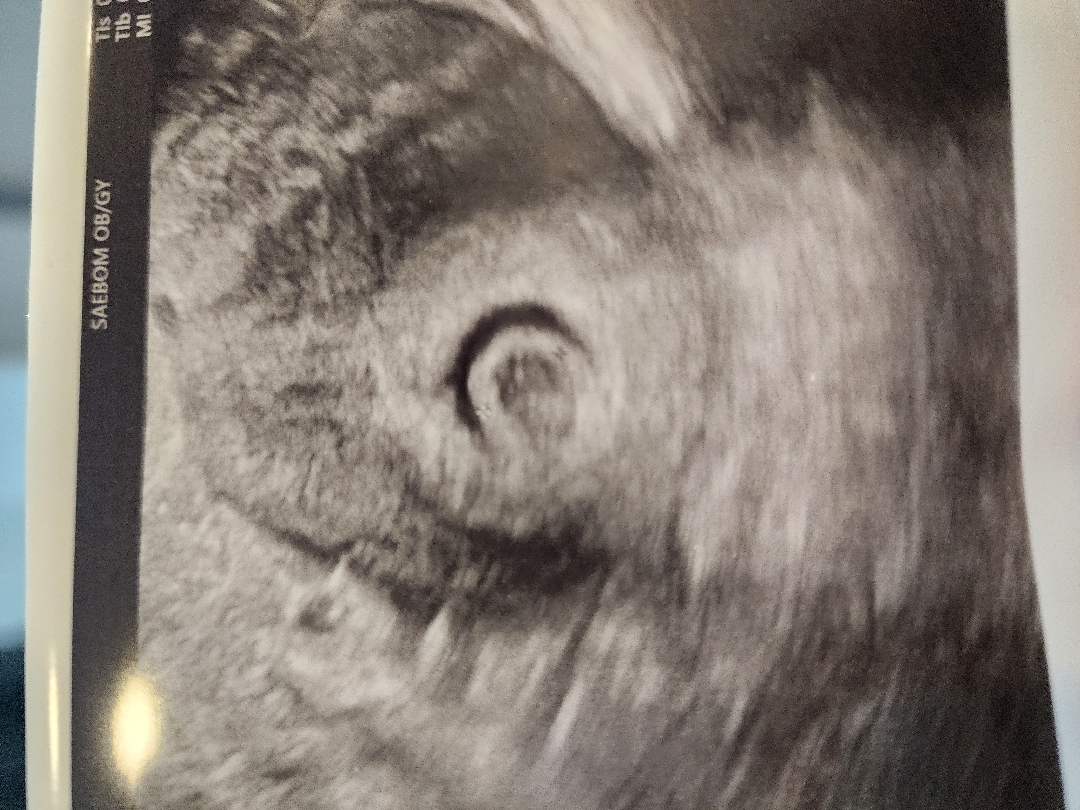

6주인데 피고임 있는데 안전하게출산하신분있으신가요???ㅜ.. 목요일에 유산방지주사맞았고 토요일에 또오라고하네요 초음파상 심각한수준인가요? 1차병원도 2차병원도 예후가안좋다고만하시네요

피고임이 꽤커보여요... 초반에는 착상되어잇더라도 피가 자궁내로 흡수되지않고 나올때 아기도 같이 쓸려나갈수도 있데요. 저도 비슷한 경험 있어서 의사쌤이 절대안정 하라고 했었어요.